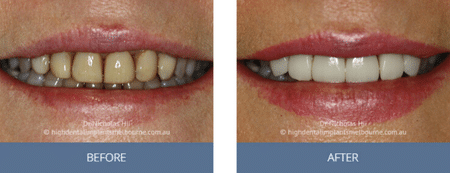

Clinical Before and After Photos

At High Dental, we believe a great smile changes everything. Our Smile Gallery showcases before-and-after images of patients who trusted us with their smiles. From veneers and crowns to full-arch implants, each result is unique — and each started with a consultation. Scroll through and imagine the possibilities for your own smile.

Images are provided for illustrative purposes only. Results shown relate to specific patients and individual outcomes may vary. A consultation is required to determine suitability for treatment.